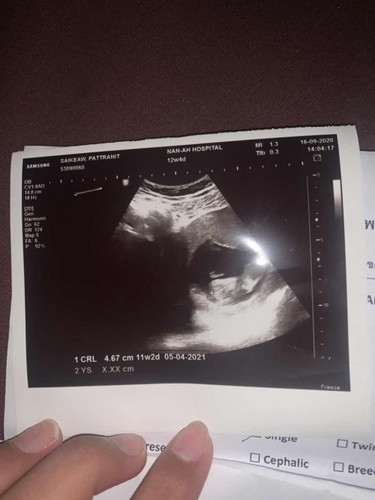

อัตราซาวด์คชาดเคลื่อนได้กี่วันคะ ถ้าอยู่ได้ 11-12 weed

ยุดหลักอันไหนคะ 12 weed 4 day หรือ 11 week 2 dauy

ใบซาว12w4d แล้ว11w2dแม่นับจากอะไรคะ